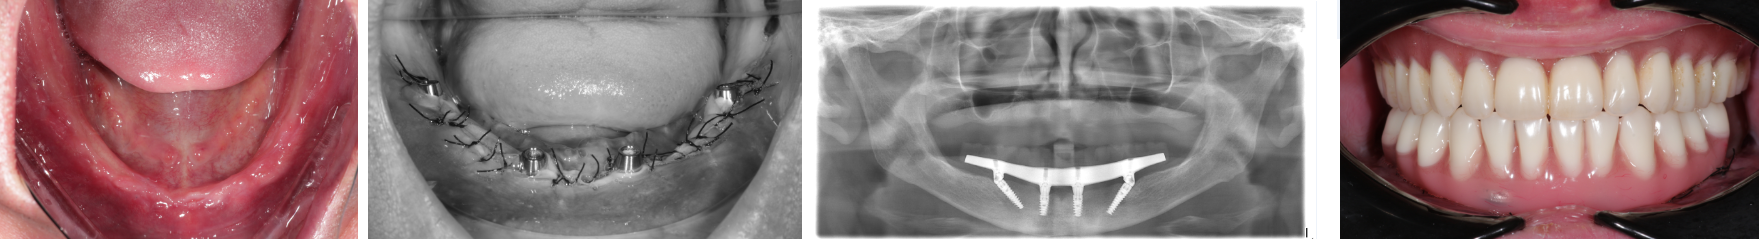

Пациент В

При помощи 3D моделирования,

конструкция для немедленной нагрузки

изготавливается до операции. Протез

можно установить в день операции или в

течении недели после нее. Временный

протезный аппарат с облегченными

искусственными коронками, с встроенной

внутренней жесткой конструкцией

стабилизирует имплантаты.

Немедленная нагрузка

важна для процесса остеоинтеграции чем

раньше кость будет получать нагрузку,

тем быстрее приживутся имплантаты.

Временный протез накладывается сроком

до 6 месяцев. Далее идет замена на

постоянную конструкцию.